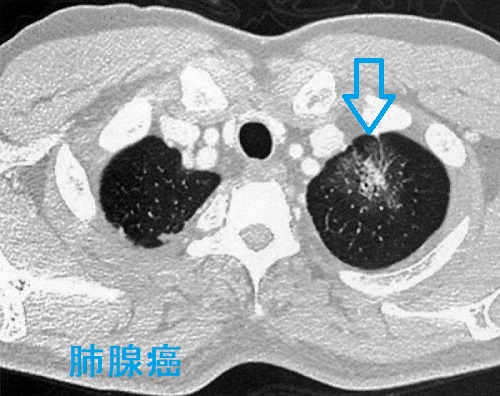

肺腺癌

原発性肺腺癌は末梢肺に発生する場合が多く、粘膜下病変主体であるため喀痰細胞診で診断できる可能性は低い。気管支鏡検査で病理組織を採取すれば確定診断できる。

肺腺癌 CT画像